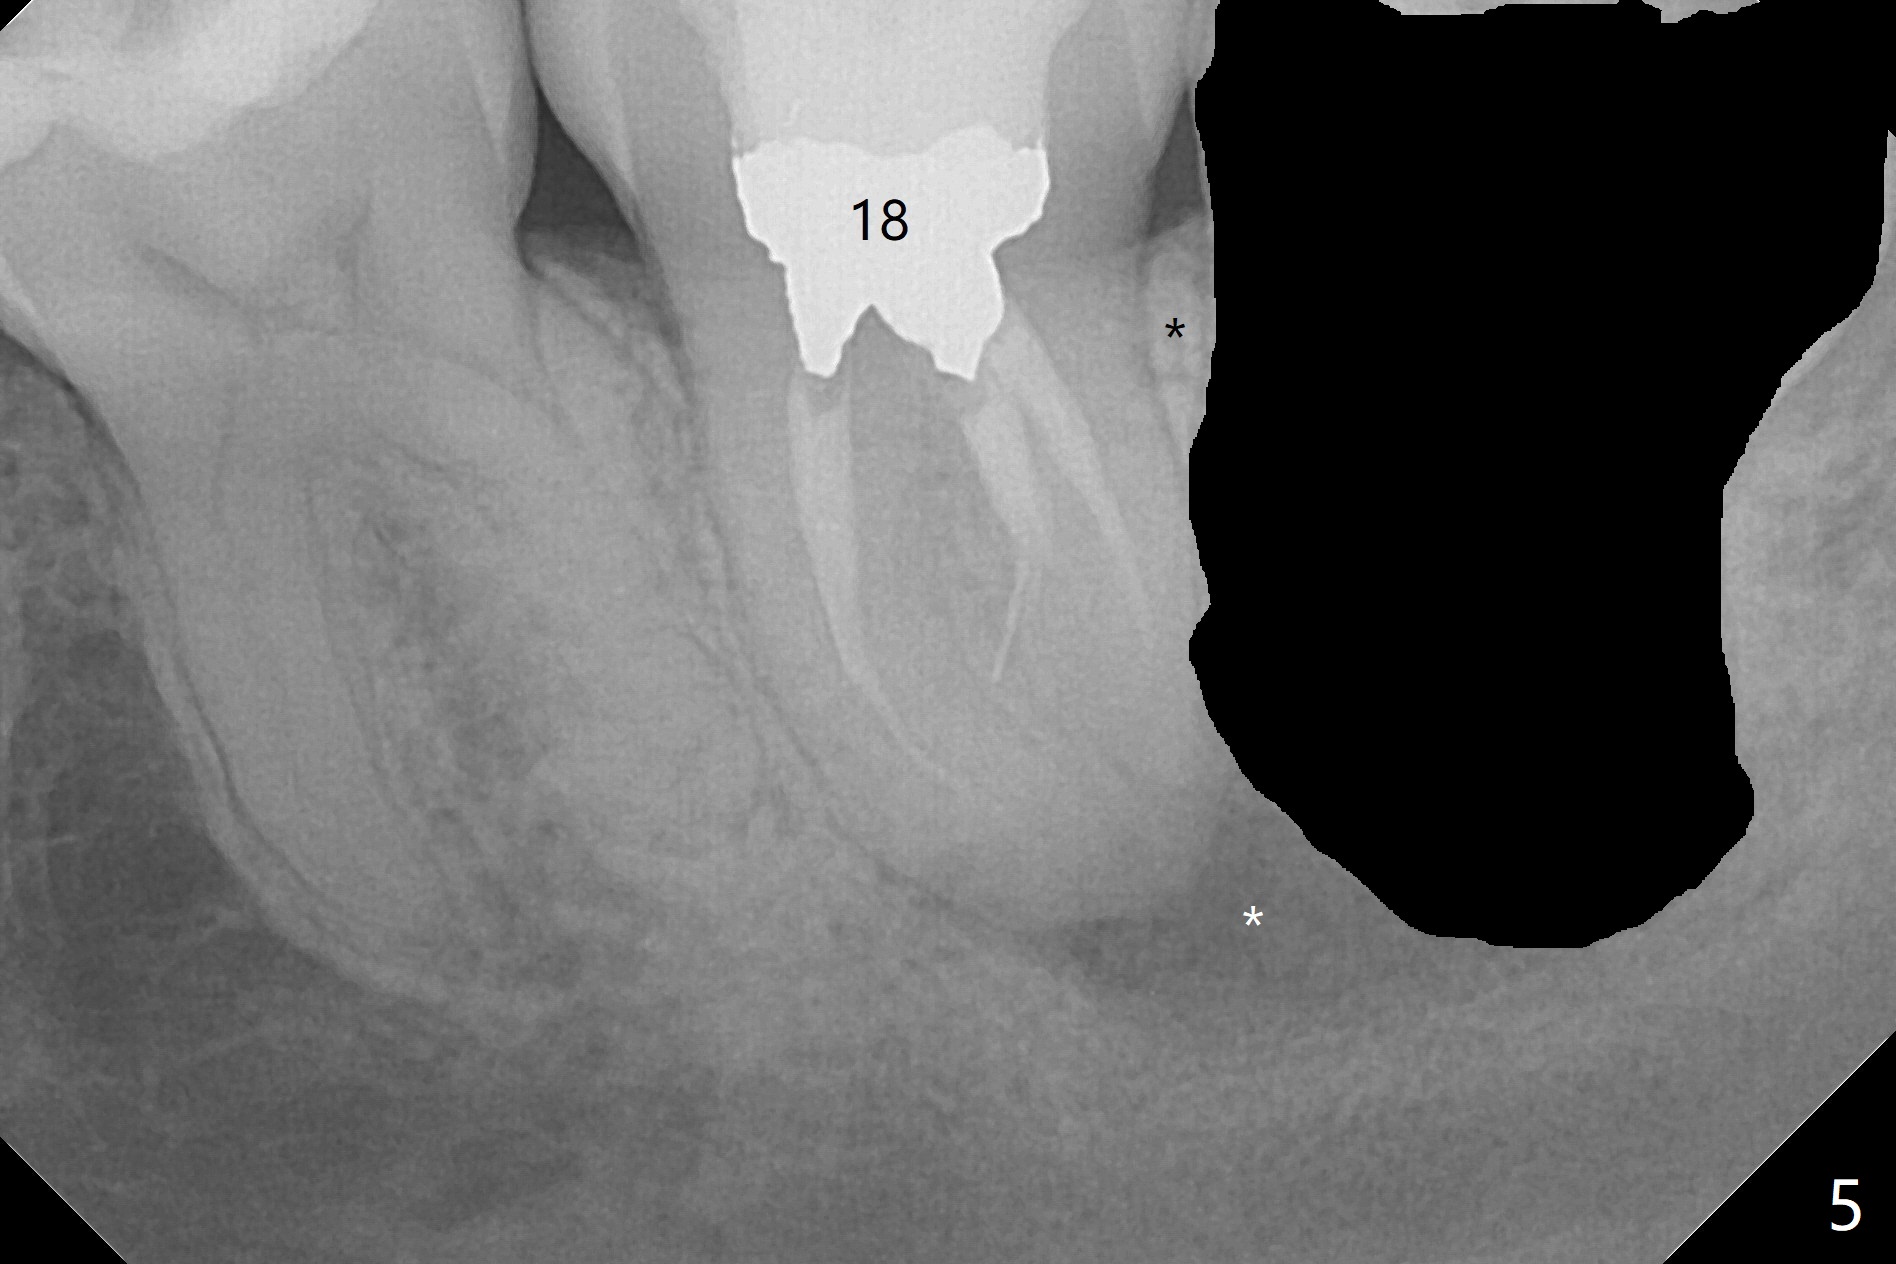

RCT Retreat, Apical Surgery Before 3rd Molar Bone Graft

A 37-year-old woman requests extraction of the 3rd molars and orthodontic retreatment (Fig.1). Since the bone between #17 and 18 is thin and short (Fig.2 black *), bone graft is needed after #17 extraction. But the apical infection at #18 (Fig.2 white *) may affect graft survival. The patient agrees to have RCT retreatment done (Fig.3 white curved lines) before extraction (black area). The apical granulation tissue can be removed (Fig.4 red area) prior to bone graft (Augma). The latter will be also placed at #17 as a control. After endodontic consultation, the patient does not want RCT retreatment. She would like to have the 3rd molars extracted first and #18 removed if needed. After #17 extraction (Fig.5), apicoectomy will be performed at #18 (Fig.6 (white outline: surgical bur, use non-torque handpiece)). Following curettage of the apical lesion at #18 (Fig.7), bone graft will be placed (Fig.8 red circles). In fact the patient insists upon #1, 16, 17, and 32 extraction. After extraction, allograft (Fig.9 A (Ossogen, Mineralized Cort/Can (30%/70%), .25-1.0 mm) is placed in the mesioapical of the sockets of #17 and 32, while Osteogen Plug (O) and BioXclude in the distocoronal one (4-0 PGA suture). There is minimal bone between the 2nd and 3rd molars (black arrowheads). The allograft is intentionally pushed into #18 apical defect after enucleation (white arrowhead). The sockets are slightly open, although sutures are in place 2 weeks postop (Fig.10,11). It is unknown whether the bone graft is partially dislodged or not.